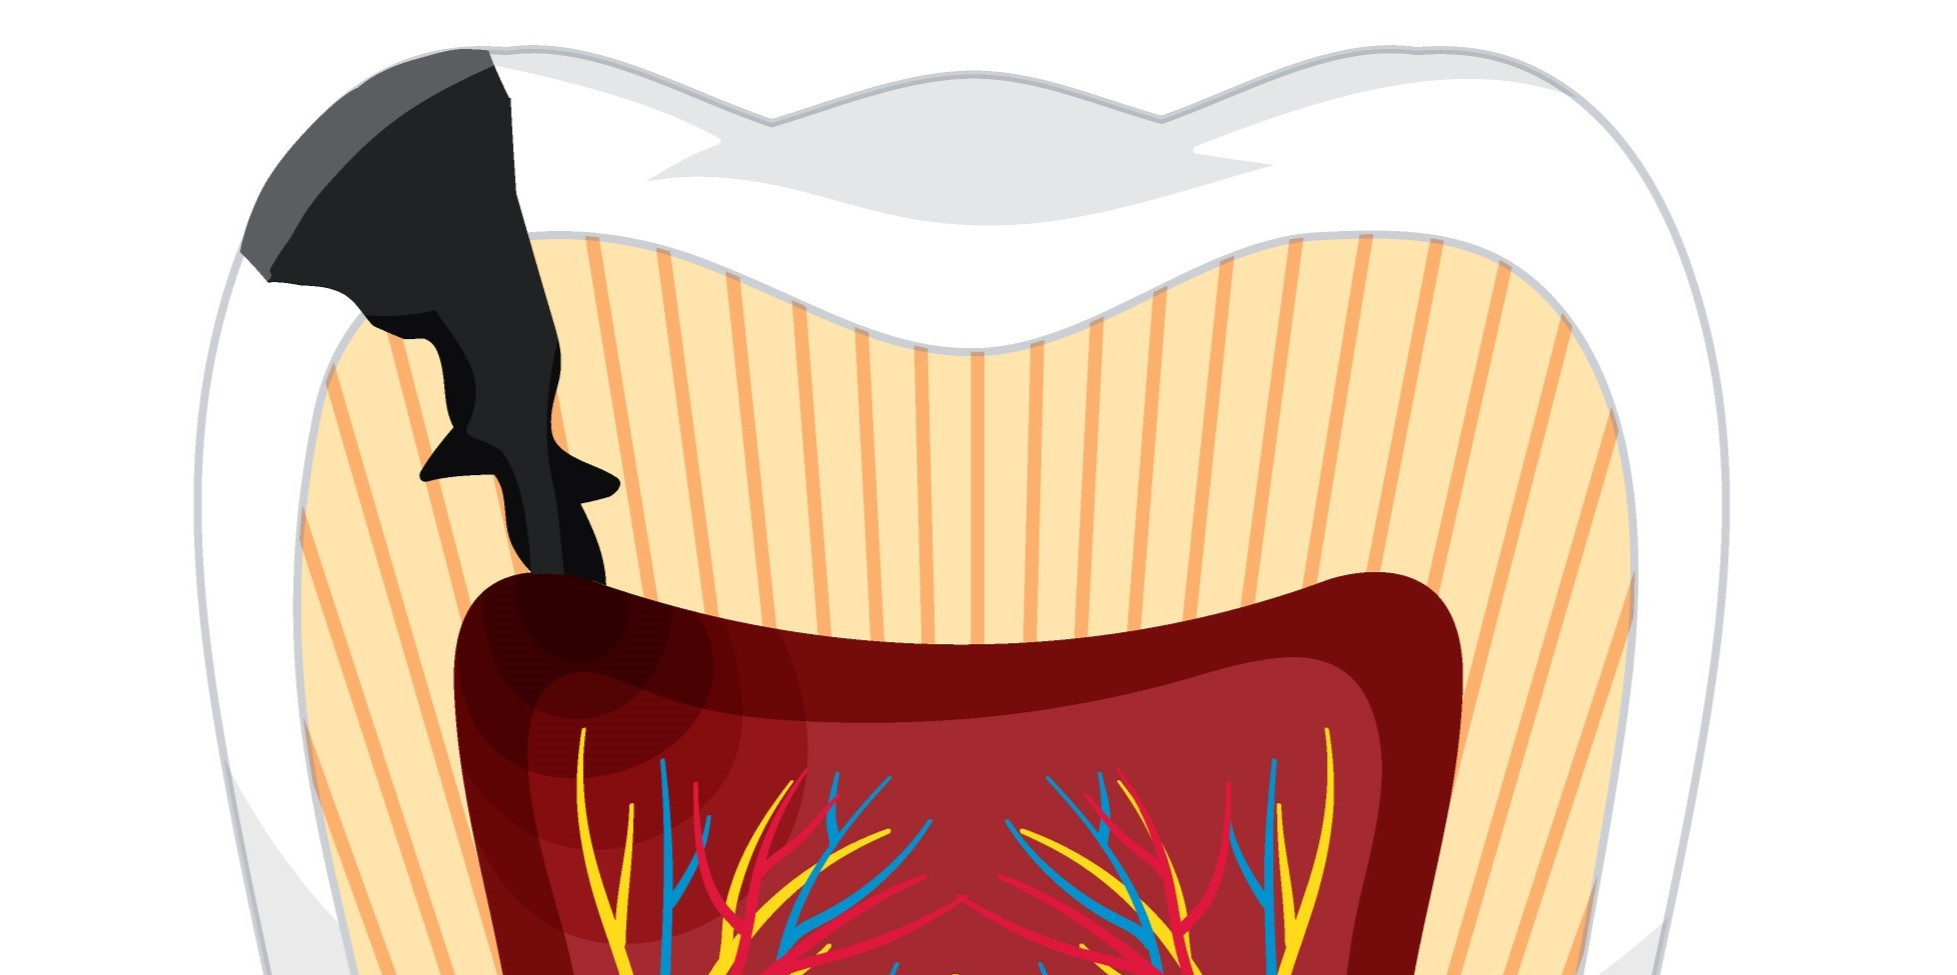

Pulpitis

Pulpitis adalah peradangan pada pulpa yang nyeri. Pulpa sendiri adalah jaringan lunak gigi yang paling dalam

Periodontitis

Periodontitis adalah peradangan pada gusi yang merusak gigi, jaringan lunak, dan tulang penyangga gigi.